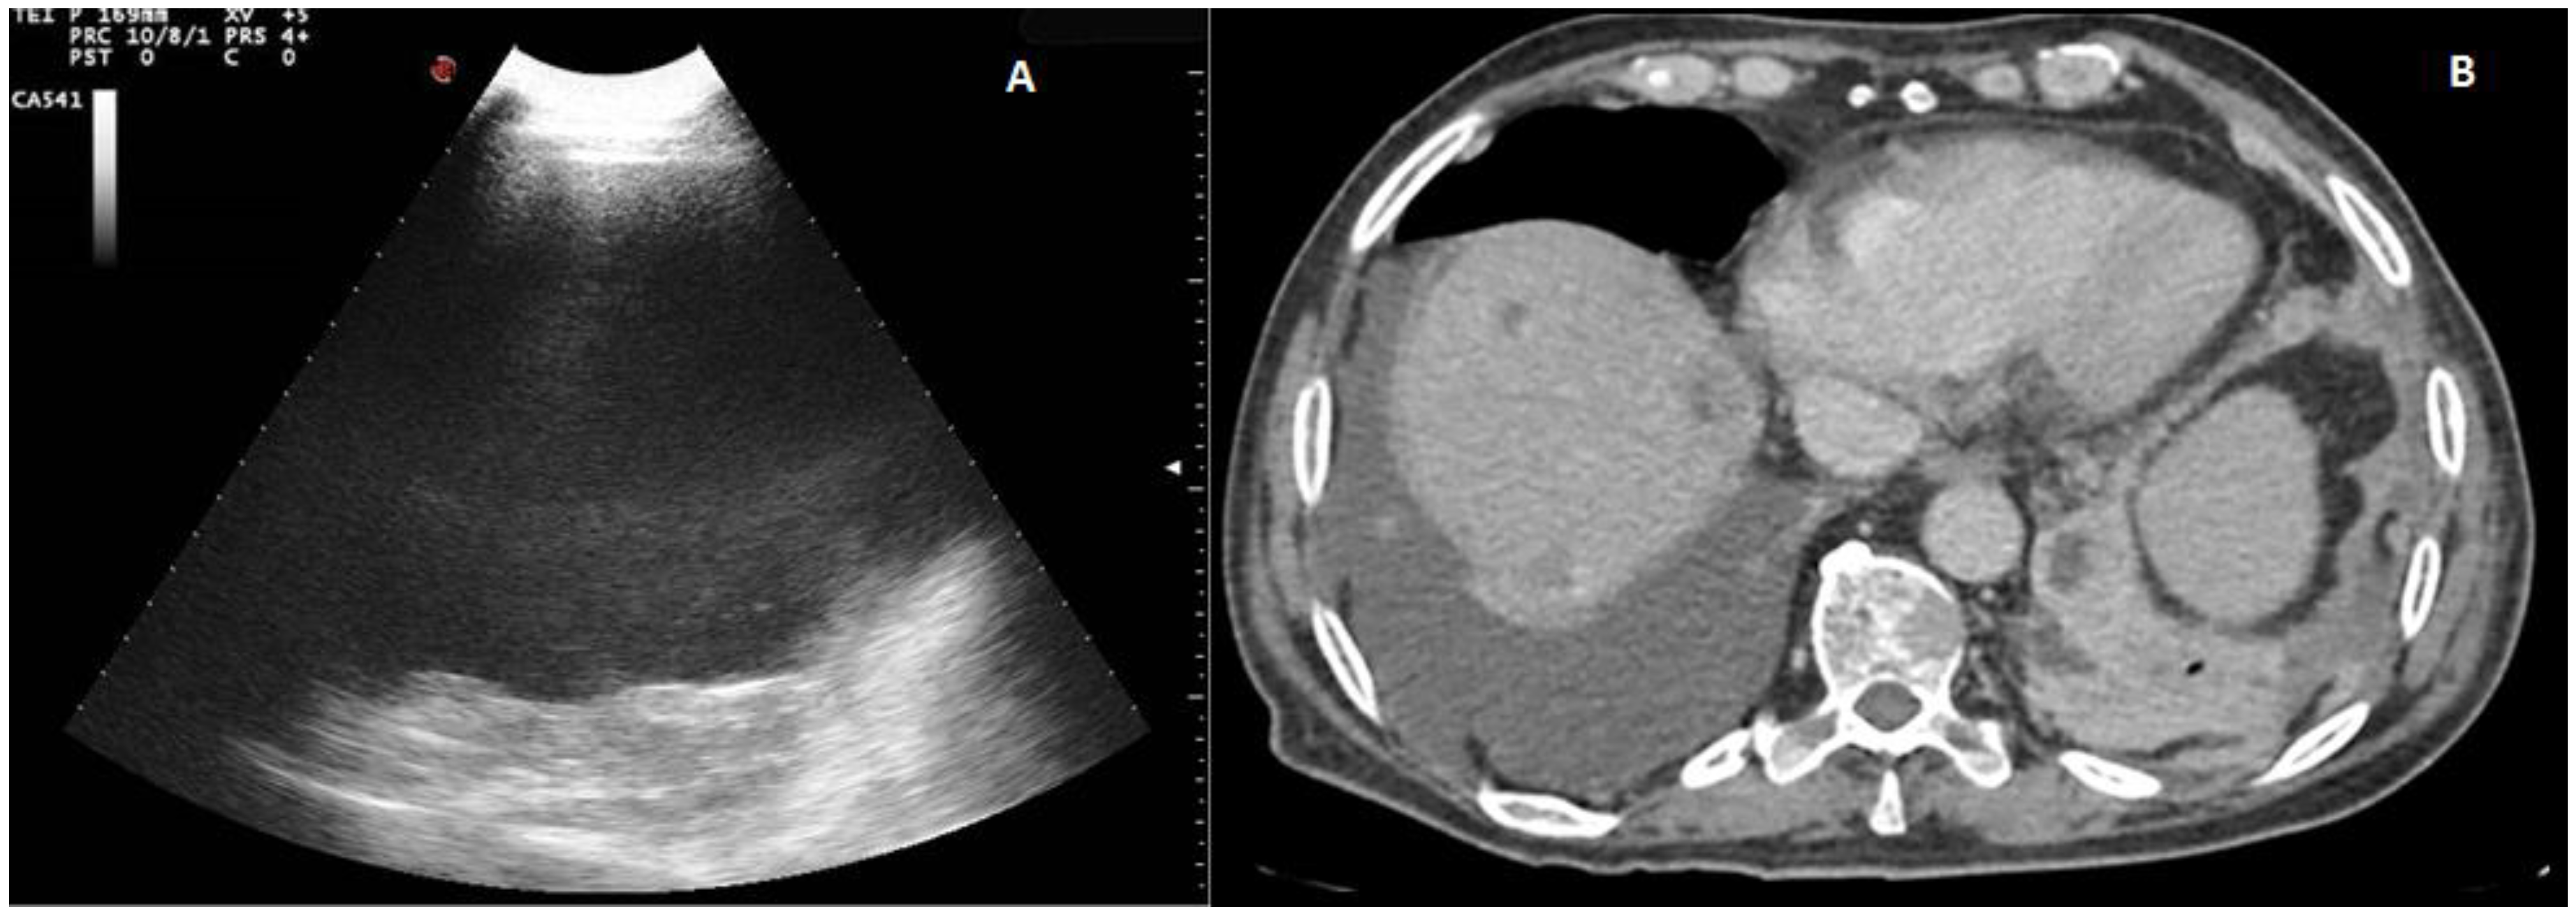

Figure 3. A complex nonseptated pleural exudate in a patient with pneumonia, measured by two orthogonal views (longitudinal and transversal), viewed by longitudinal scan using a convex multifrequency probe (3.5 MHz).

Only the exudative effusions showed a complex nonseptated or a hyperechoic TUS appearance. Considering the pleural effusions classified as exudates, the frequency distribution of the anechoic TUS appearance (n = 138/334, 41.32%) and of the complex nonseptated pattern (n = 174/334, 52.09%) were statistically higher than that of the homogeneous hyperechoic one (22/334, 6.59%), with a p-value < 0.0001. The number of complex nonseptated exudates was statistically higher compared to that of the anechoic ones (p = 0.005) (Figure 3).